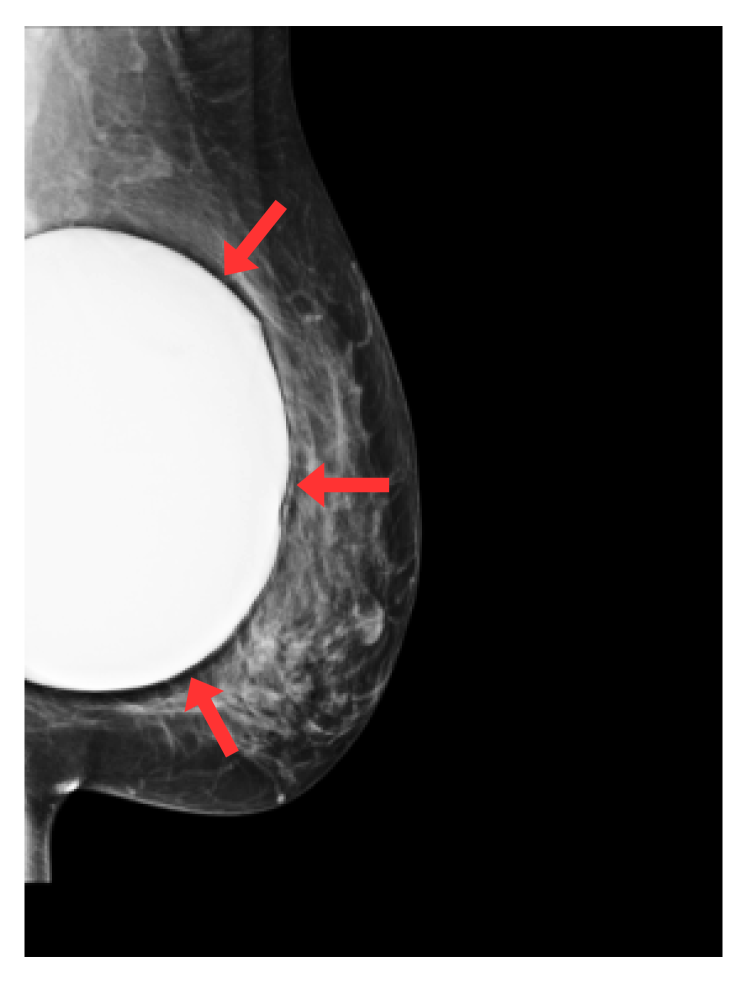

Refer to caption

(c) Breast implant

Fig. 1: Radio-opaque artefacts considered in this study: skin markers (circle and triangles), breast implants, support devices (e.g. pacemakers) and spot compression (or magnification) devices. Red arrows highlight artefacts of interest.

We focus on five types of artefacts: (a) circular skin markers, (b) triangular skin markers, (c) breast implants, (d) devices (e.g. pacemakers), (e) compression and special magnification artefacts. Examples of such artefacts can be found in Fig. 1. Circular and triangular skin markers are radio-opaque markers placed on the breast skin by radiologists at acquisition time [8], indicating locations of moles (circle) or a palpable mass (triangle). Breast implants and devices such as pacemakers or metallic sensors appear as large, very high contrast structures on the mammograms. Similarly, spot compression and special magnification devices are large radio-opaque structures surrounding the breast area, allowing magnification of small, suspicious regions of breast tissue. Despite their clear effect on image appearances, the effect of the presence of such artefacts in mammograms on downstream task models (e.g. breast cancer screening) has - to the best of our knowledge - not been studied so far. This is largely explained by the fact that labels indicating the presence of such artefacts within an image are not typically available in current publicly available mammography datasets.